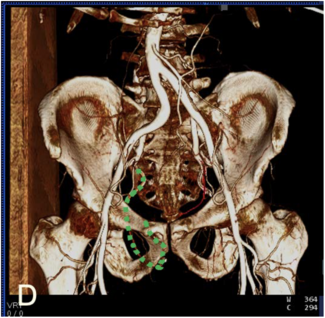

A 50-year-old man with a medical history of active smoking and diagnosed with type 2 diabetes mellitus was admitted to the ED complaining of sudden acute chest and left groin pain lasting 1 hour.